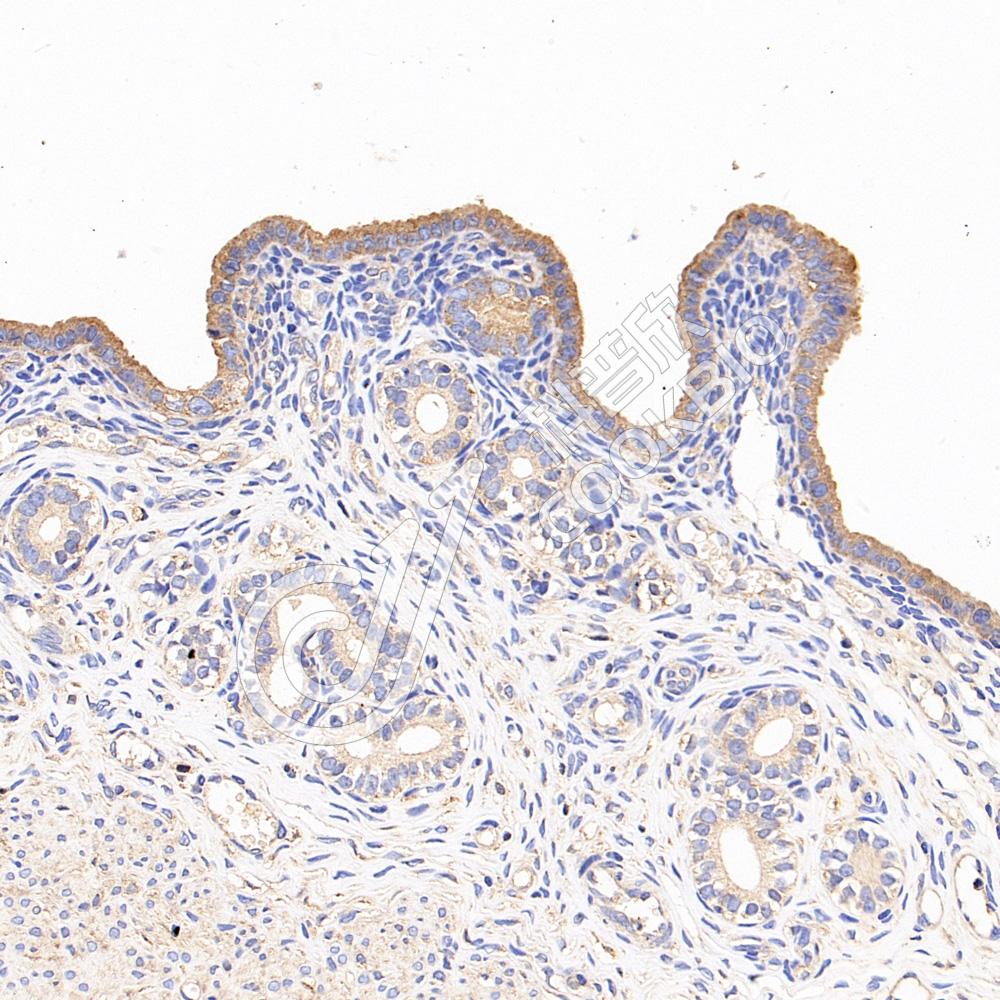

IHC检测CD133蛋白(货号 K236180).

样品: 大鼠子宫, 4%多聚甲醛 (货号KSG1101) 固定12-24小时.

抗原修复: 柠檬酸抗原修复液(干粉, pH 6.0) (KSG1201), 高压锅均匀喷气计时2分钟.

—抗: 1: 500稀释, 4℃ 孵育过夜.

二抗: S-vision免疫组化多聚二抗(山羊抗小鼠), 即用型(货号KB3903), 室温孵育20分钟.